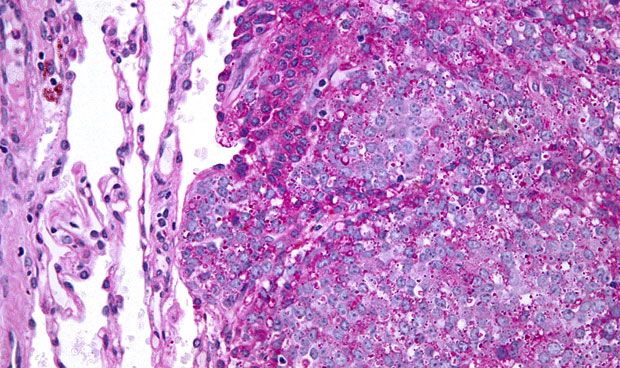

En concreto, y aunque existen más de 150 variedades de sarcomas reconocidas por la Organización Mundial de la Salud (OMS), hay dos grandes grupos de sarcomas: los de partes blandas (SPB), que se desarrollan en los tejidos blandos del organismo como los músculos, tendones o grasa; y los sarcomas óseos (del esqueleto). Concretamente, los tumores del estroma gastrointestinal (GIST) son técnicamente sarcomas de partes blandas, pero se consideran aparte por sus características diagnósticas y terapéuticas especiales.

Los sarcomas y, en particular, los GISTs han experimentado importantes avances en su diagnóstico y tratamiento en los últimos años, dado que los GIST han pasado en menos de 10 años de ser tumores mal identificados y resistentes a la quimioterapia convencional, a convertirse en una entidad biológica e histopatológicamente bien entendida y distinguible de otros sarcomas.

Tras la aparición en el tratamiento de los GIST de los fármacos dirigidos contra dianas moleculares, como el imatinib y el sunitinib en enfermedad avanzada, el imatinib durante tres años en la enfermedad localizada de alto riesgo ha demostrado el aumento de supervivencia de estos pacientes.